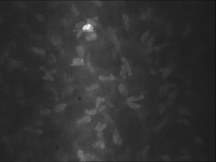

The human corneal endothelium is a single layer of 400,000 to 500,000 cells. Confocal microscopy provides views of this cell layer that surpass the details seen under specular microscopy (Figs. 19 and 20). Cells are 4 to 6 μm in height and 20 μm in width, and their posterior surfaces are predominantly hexagonal when viewed under specular microscopy (Fig. 21). Cross-sectional views with electron microscopy show that cell lateral walls are extremely tortuous and interdigitate with extensive folds and finger-like projections. It has been estimated that the total paracellular path length may be 10 times longer than the total height of the cell.90 Numerous gap junctions along the lateral membranes provide cell-to-cell cytoplasmic communication as evidenced by the presence of connexin 43 and the spreading of fluorescent dye from an injected cell to surrounding cells (Fig. 22).91

Fig. 19. Confocal microscopic transverse image of the human corneal endothelium in vivo. In the young normal cornea, the majority of the cells will have a hexagonal outline and they will be fairly uniform in size. The dark spots near the center in many of the cells may represent the central endothelial cilium (500×). (Courtesy of Nidek Technologies.)

Fig. 20. Confocal microscopic transverse image of the human corneal endothelium in vivo after penetrating keratoplasty. Note cellular enlargement, polymegathism, and polymorphism. Cell nuclei are clearly visible. Normally non-dividing, endothelial cells enlarge slowly with age to compensate for cell loss, maintaining a continuous lining on Descemet's membrane. Cataract surgery and transplants generally exhibit cell loss. Below about 400 cells per mm2 endothelial decompensation can occur with ensuing edema (500×). (Courtesy of Nidek Technologies.)